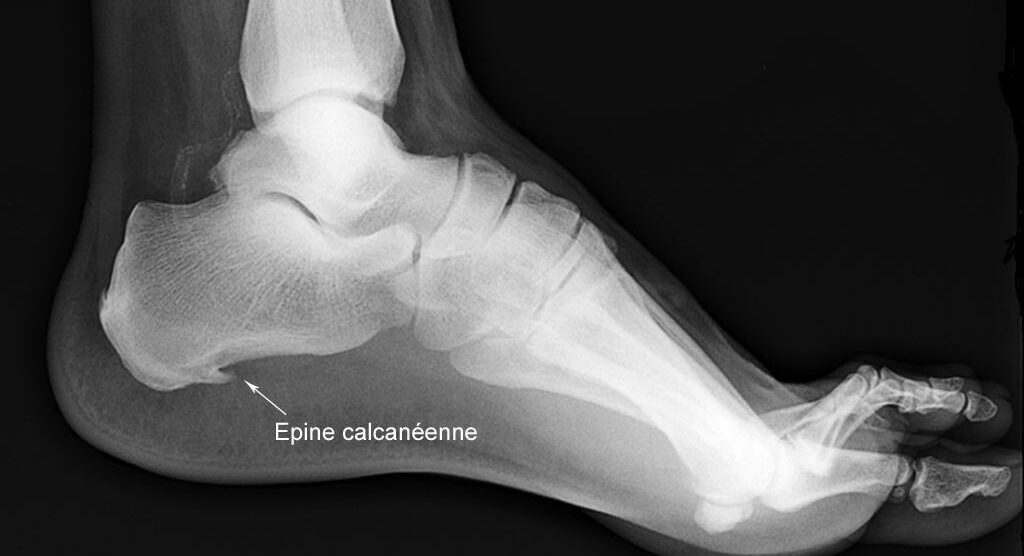

L’épine calcanéenne, ou épine de Lenoir, est une petite excroissance osseuse qui se forme sous […]